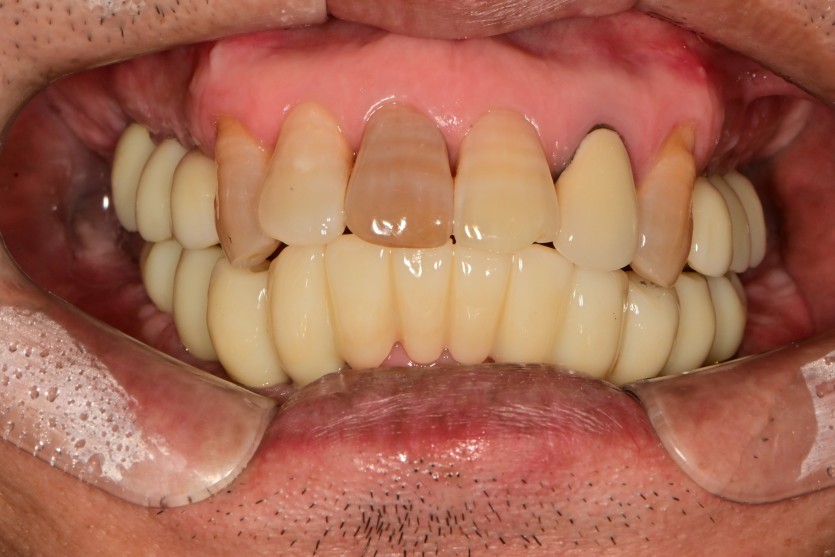

하악 전체 임플란트 증례입니다.(상악 일부)

14개의 임플란트로 완성하였습니다.